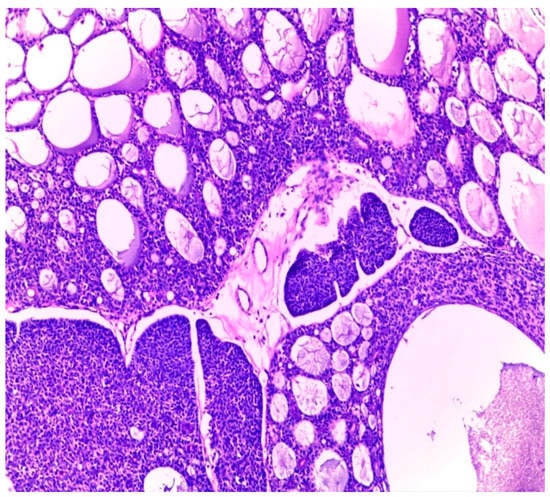

Histologically, salivary nonsolid AdCCs showed biphasic cell populations arranged in alternate cribriform and tubular architectures (Figure 1). The cribriform pattern demonstrated nests of neoplastic cells with hyperchromatic, angulated nuclei arranged in microcystic and macrocystic spaces. These pseudocystic cavities were occasionally filled with hyaline or basophilic mucoid material. The histologic features in the major salivary glands did not differ much from those in the minor salivary glands. However, solid nests of AdCC favored submucosal infiltration in the minor salivary glands (Figure 2, Case #15). Sinonasal AdCC revealed nests of cribriform and solid areas, while extensive hyalinization was recapitulating a jigsaw puzzle-like pattern (Figure 3). The cells of sinonasal AdCC were sometimes basaloid, with dark, hyperchromatic nuclei. The cells were typically arranged in a palisading pattern around the cystic spaces. A few salivary AdCCs revealed basaloid cells arranged in solid growth patterns that were insufficient for diagnosis as high-grade AdCCs. Mammary SB-AdCC revealed areas of cribriform, a solid growth pattern (>90%), and a basaloid appearance, with myxoid or hyalinized stroma. Ductules were present within the tumor islands. Small cysts and pseudoglandular structures were occasionally seen (Figure 4). This variant is characterized by the presence of small, basal-like cells with scant cytoplasm. The basaloid variant was associated with a higher risk of metastasis and a poorer prognosis. All neoplastic cells were positive for IHC SOX10, CK7, CD117, p63, and KI67. The clinical and molecular findings are shown in Table 1. There, all of the AdCC cases had MYB rearrangements detected by fluorescence in situ hybridization (FISH), which is a common genetic alteration observed in AdCC. Specifically, MYB was found to be fused with NFIB and/or KMT2C/KMT2D in AdCC cases from sinonasal and minor SG sites. MYB::NFIB fusion is a well-known molecular alteration that occurs in approximately 30–70% of AdCC cases and has been associated with better prognosis compared to cases without this fusion. On the other hand, MYB::KMT2C/D fusions were less common but have also been reported in cases from salivary and sinonasal AdCCs. Although this is the first study to report this finding, its clinical significance is yet to be fully elucidated. In addition to FISH, some AdCC cases were also analyzed using next-generation sequencing. In Table 1, NGS was performed in several AdCC cases from sinonasal, minor SG, and parotid gland sites. MYB::NFIB and MYB::KMT2D fusions were detected in these cases, which is consistent with the FISH results. Notably, some cases were not analyzable by NGS, which may be due to various reasons such as low DNA quality or quantity. The median score for Group 1 was 70 (IQR: 60–80), the median score for Group 2 was 85 (IQR: 75–90), and the median score for Group 3 was 60 (IQR: 55–70). The results indicate that there was a significant difference between Group 1 and Group 3 (p < 0.05) and between Group 2 and Group 3 (p < 0.05) but not between Group 1 and Group 2 (p > 0.05). This suggests that the solid mammary AdCCs with basaloid features (Group 3) have different characteristics compared to the other two groups.

Figure 3.

Sinonasal AdCC revealed nests of cribriform and solid areas, while extensive hyalinization was recapitulating a jigsaw puzzle-like pattern (H&E stain; magnification ×5).